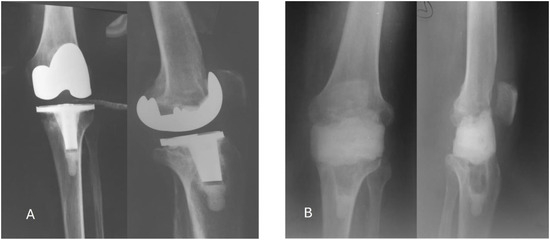

The objective of this case report is to describe the surgical management of a 68-year-old male patient who had undergone total knee replacement and subsequently developed a late local periprosthetic infection. The patient presented at approximatively one year postoperatively with symptoms indicative of a late periprosthetic septic complication, including, pain, local edema, elevated temperature, and loss of range of motion. Laboratory tests revealed an inflammatory response, as evidenced by elevated levels of C reactive protein (CRP) (52 mg/L), fibrinogen (440 mg/dL), and erythrocyte sedimentation rate (ESR, 27 mm/h) and no other significant modifications in blood cell count other than mild anemia, with a hemoglobin of 11.2 g/dL. Radiographs showed alterations in bone structure suggestive of implant loosening and osteolysis at the tibial level (Figure 1). The patient had no significant comorbidities. Procalcitonin testing was negative, thus the patient was not in a septic condition; blood cultures were not collected.

Figure 1. Radiological studies of the case. A. Before surgery – frontal and lateral; B. After the first surgery – frontal and lateral.